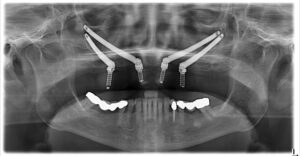

À Chirurgie Buccale Seaforth, la planification implantaire comprend :

- Imagerie CBCT 3D : visualisation précise de l’os, des nerfs et des sinus